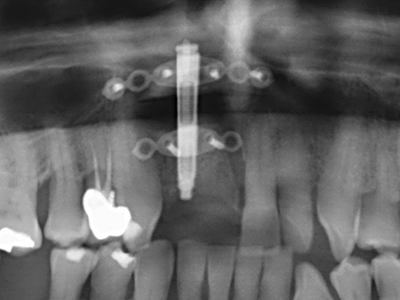

Piezosurgery has additional advantages when harvesting bone blocks. In addition to the high precision with osteotomy described above, the use of the thin saw tips specifically minimizes loss of material. Greater loss of material during harvesting can be expected with the thicker instrument tips, particularly when using Lindemann drills (Lakshmiganthan, Gokulanathan et al. 2012). The basal separation, which is necessary particularly for retromolar block transplants, is simplified by specially designed rectangular saws, with the result that piezosurgery is viewed as a precise, simple and safe procedure for harvesting retromolar bone blocks (Happe 2007) (Fig. 1-12).